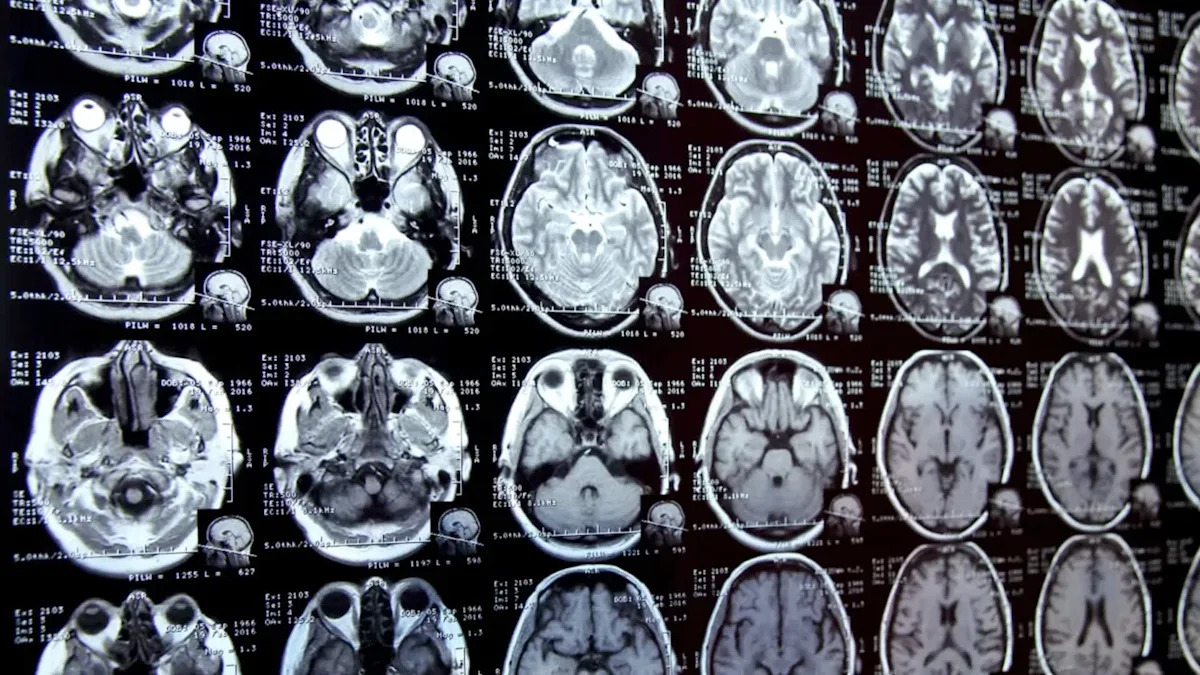

Son elmi tapıntılar geyim, qablaşdırma və şinlərdən qopan mikroskopik plastik hissəcikləri — mikroplastikləri və nanoplastikləri insan beynində aşkarlayıb. Bu hissəciklər qan dövranı ilə hərəkət edərək beyin xəstəlikləri üçün xarakterik olan iltihab reaksiyalarını tətikləyə bilir. Mütəxəssislər, daha kiçik hissəciklərin ağciyərlər və burun vasitəsilə, qoxu hissi üçün istifadə olunan sinirlər vasitəsilə beyinə çatdığını bildirirlər. Tənəffüs sağlamlığına dair əlaqəli tədqiqatlar, plastik tozun nəfəs alınmasının nə qədər geniş yayıldığını göstərir.

İnsan beynində və ya bədənin hər hansı bir hissəsində plastik maddələrin olması normal deyil. Plastiklərin tərkibində bisphenol A (BPA), per- və poliflüoroalkil maddələr (PFAS) və ftalatlar kimi tonlarla kimyəvi maddə var ki, bunlar məhsullara möhkəmlik və elastiklik verir. Lakin bu kimyəvi maddələr hormonları pozaraq əhval dəyişikliklərinə səbəb ola və beyin inkişafını ləngidə bilər. Bu kiçik mikroplastiklər, zehni və beyin sağlamlığına təsir edə bilən bir neçə ətraf mühit stress faktorundan yalnız biridir. Məsələn, bəzi araşdırmalar istiliyin psixiatrik dərman qəbul edən şəxslərə necə təsir etdiyini göstərir, digərləri isə hava çirklənməsini uşaqların beyin inkişafı ilə əlaqələndirir. Mikroplastiklər həm ətraf mühitdə, həm də insan orqanizmində zamanla toplanır. Bir plastik çubuq iki əsrə qədər qala bilər. Təxminlərə görə, insanlar həftədə su, qida və digər mənbələr vasitəsilə beş qrama qədər mikroplastiklər qəbul edirlər.